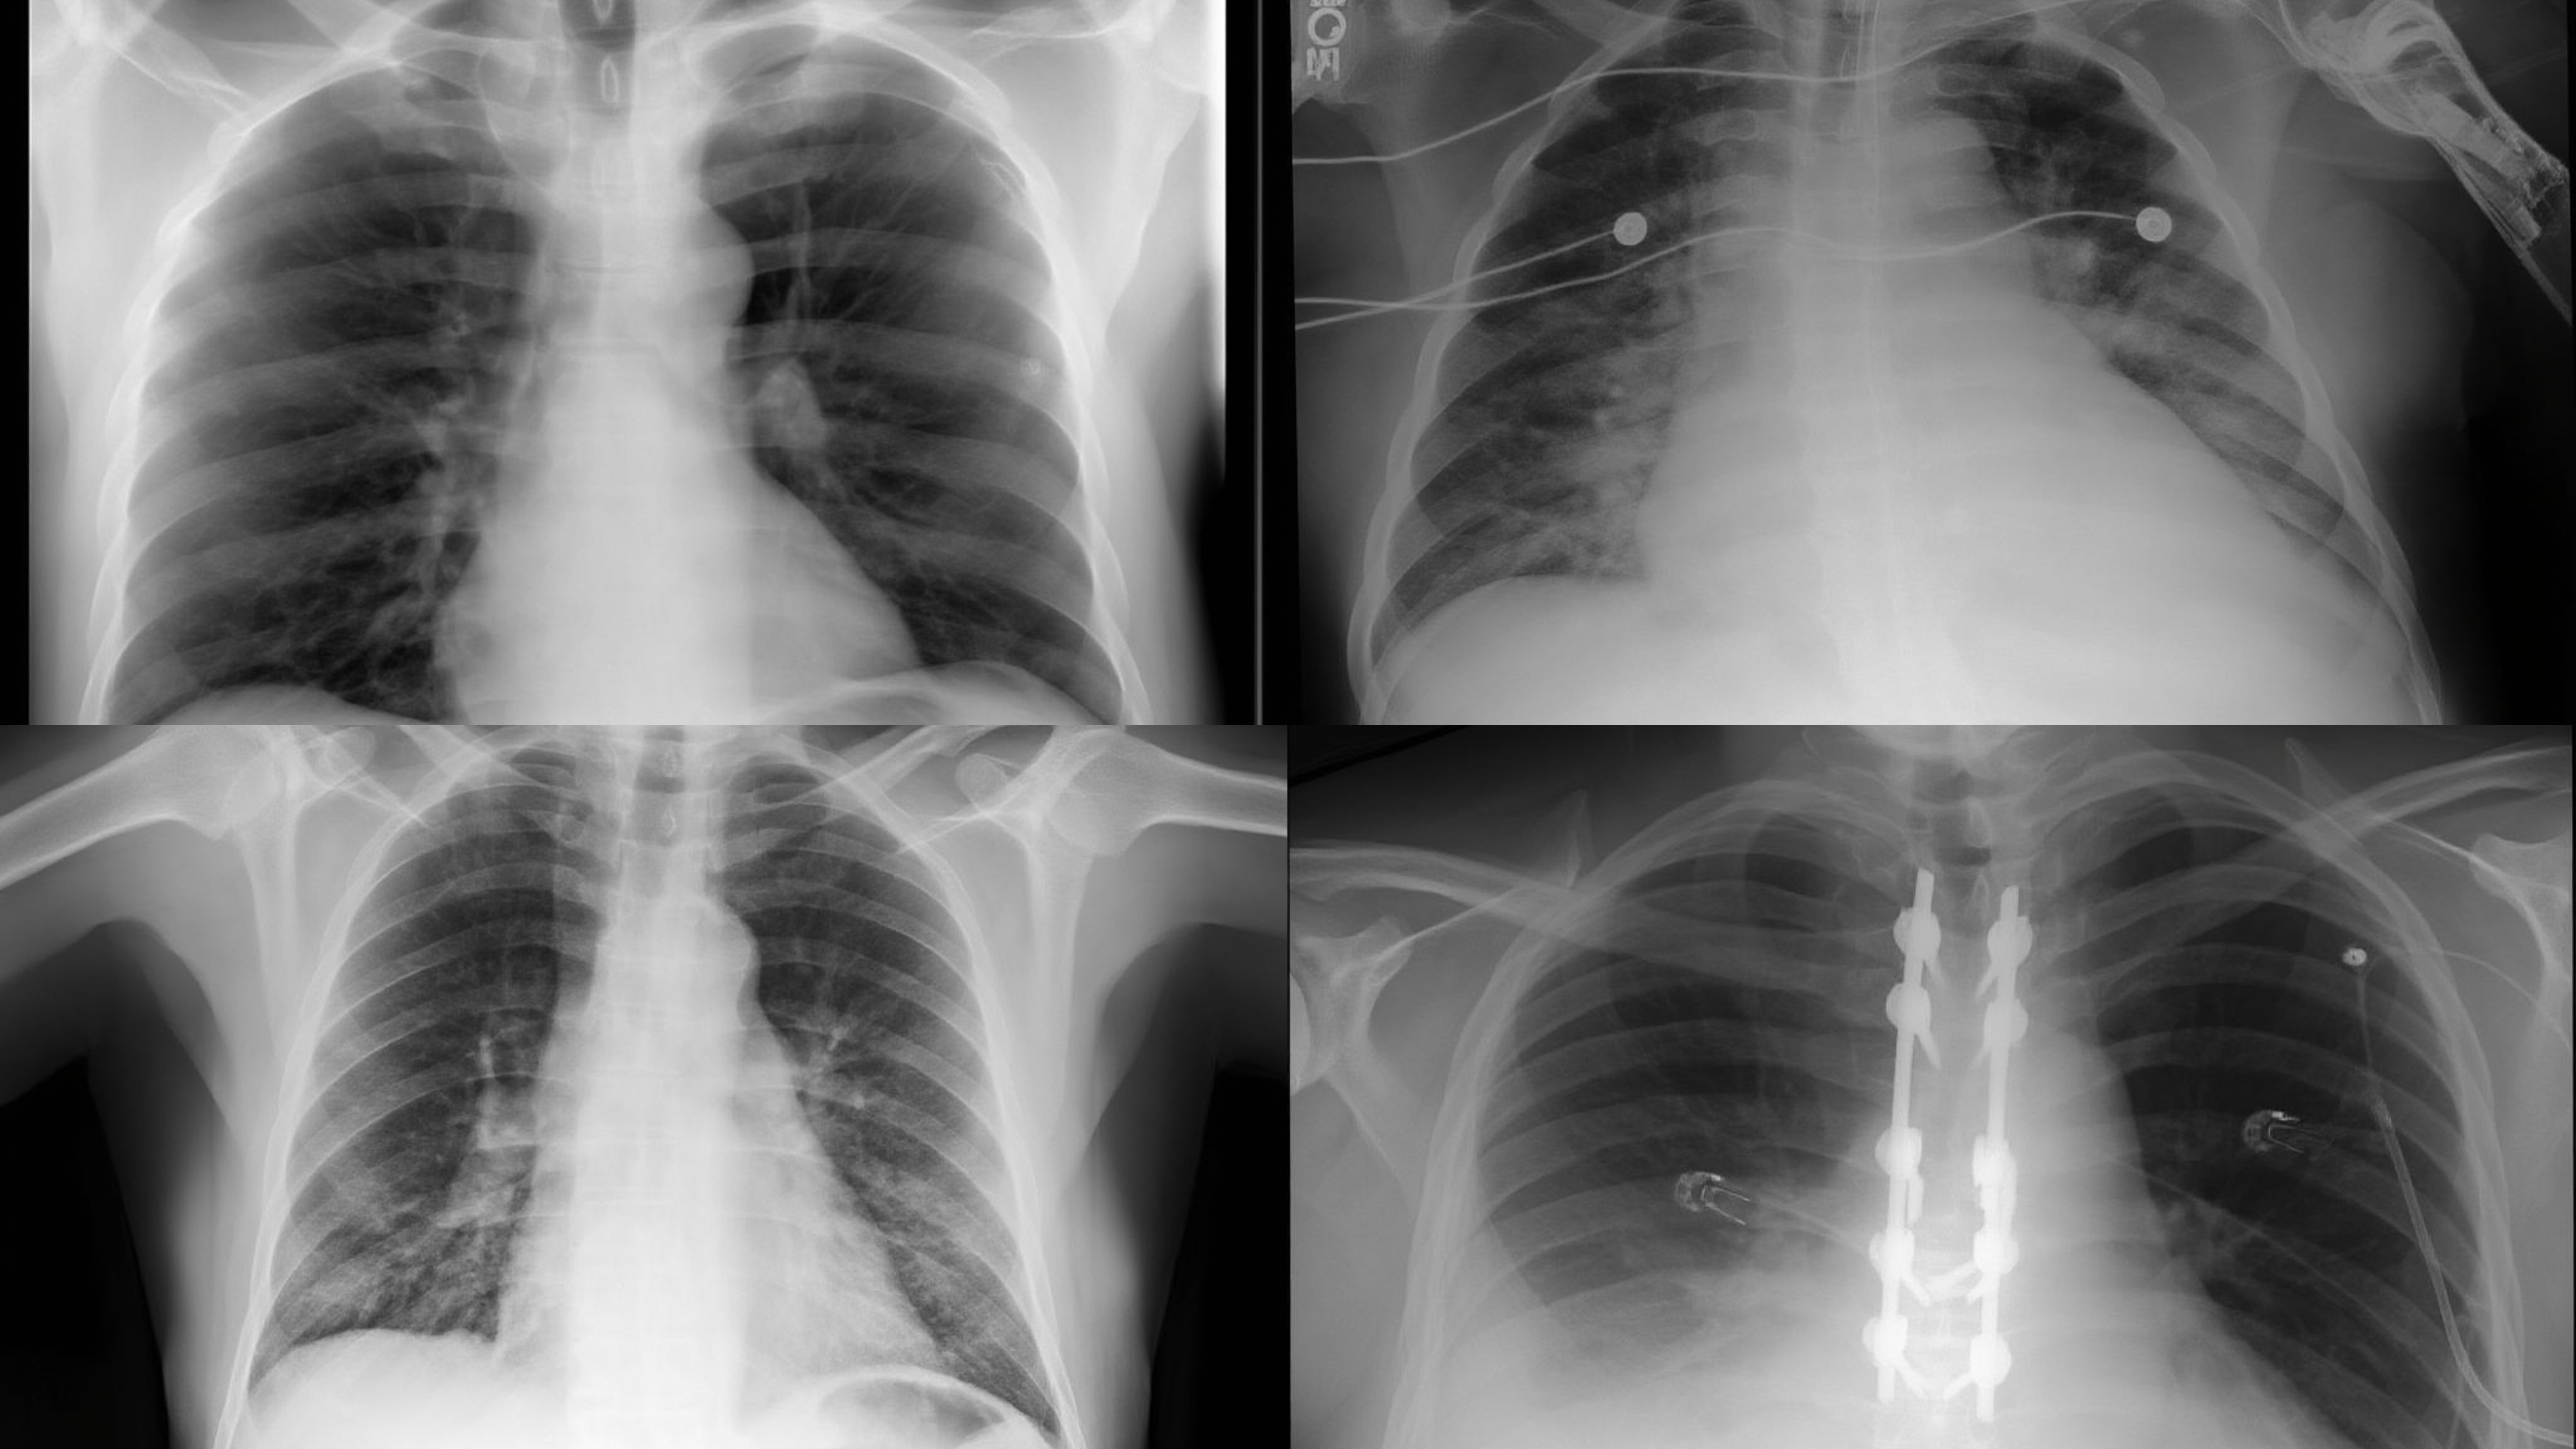

Chest X-Ray (CXR)

Text-to-image generation performance across 8 medical imaging modalities. Metrics: gFID β (lower is better) / BioMedCLIP Score β (higher is better)

| Model | CFP | CXR | CT | HIS | MRI | OCT | Ultrasound | Endoscopy | Average |

|---|---|---|---|---|---|---|---|---|---|

| Bagel (7B) | 217.19/0.650 | 182.80/0.662 | 163.78/0.652 | 206.18/0.643 | 175.74/0.639 | 307.80/0.719 | 255.78/0.672 | 214.61/0.668 | 215.49/0.660 |

| UniMedVL (14B) | 53.20/0.708 | 73.04/0.702 | 73.04/0.696 | 149.01/0.704 | 90.36/0.706 | 99.27/0.721 | 95.38/0.706 | 133.11/0.707 | 96.29/0.706 |